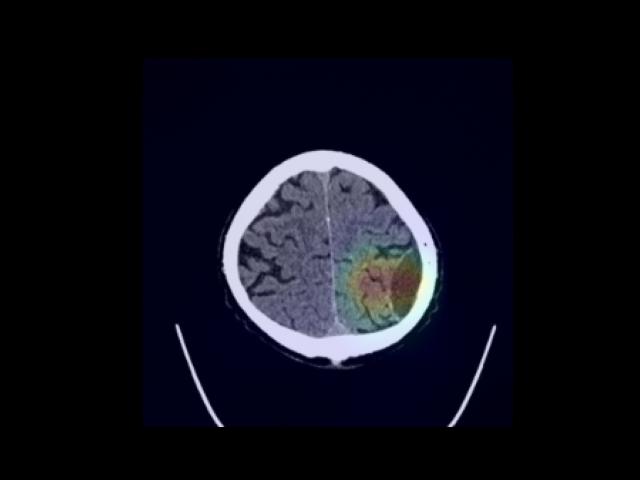

Sample Gallery